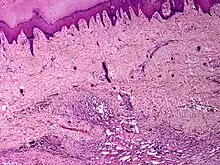

It is a vascular malformation wherein blood vessels proliferate along with accompanying mature fat and fibrous tissue, lymphatics and sometimes nerves.[2] They may involve skin, subcutaneous tissue, skeletal muscle and occasionally bone.[2]